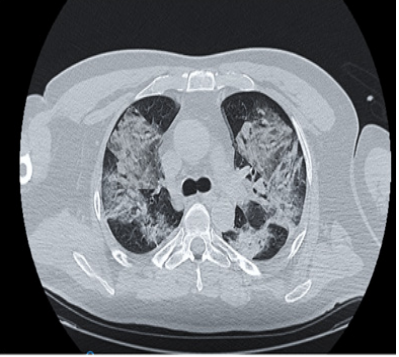

Anemia, lymphopenia, neutrophilicleucocytosis were firstly assessed; in turn piastrinopenia with high levels of D-Dimer and fibrinogen were recorded. The Il-6 value was over the normal range. Sputum was negative for opportunistic.Swab, RT-PCR and BAL fluid were negative for SARS-CoV-2. BAL fluid showed inflammatory cells with altered clung cells, neutrophil, macrophages and activated lymphocytes. The CT images of the chest, described within surgical scarring of the right lung, a pleural effusion with air bronchogram and a massive bilateral alveolar thickening with diffuse ground-glass opacities evolving into a whited out lung (Figure 1).

Figure 1 Chest CT scan of RILI case showing the whited out lung started from the irradiated right lung.